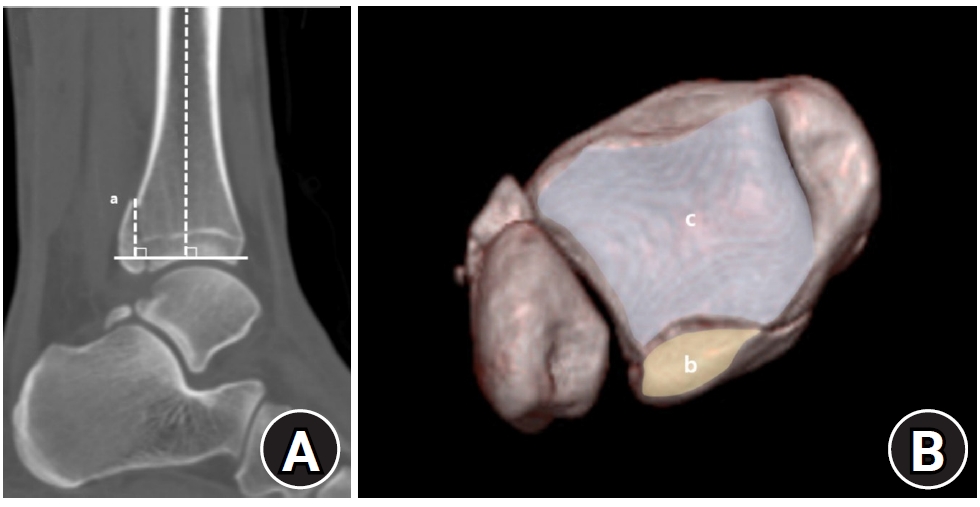

Demographic and clinical data were obtained from electronic medical records. Radiographic data were derived from 3D-CT scans. Radiographic analysis was performed using 3D-CT to assess the characteristics of both lateral and posterior malleolar fractures. Lateral malleolar fracture patterns were determined by measuring the vertical distance between the highest posterior cortex or lowest anterior cortex of the fracture and a line perpendicular to the tibial axis at the distal tibial articular surface. The angle between the posterior cortex of the lateral malleolus and the line connecting the anterior and posterior cortical points was defined as the fracture angle (Fig. 1).

Fig. 1.

Radiographic assessment of fracture characteristics. (A) Posterior height (a) and anterior height (b) represent the vertical distances from the highest point of the posterior cortex (▼) and the lowest point of the anterior cortex (▲) of the distal lateral fibula, respectively, to the line perpendicular to the tibial axis that intersects the distal tibial articular plafond. (B) The fracture angle (c) of the lateral malleolar fragment is defined as the angle between the posterior cortex of the lateral malleolus and the line connecting the anterior and posterior cortical points of the fracture.

Fig. 1. Radiographic assessment of fracture characteristics. (A) Posterior height (a) and anterior height (b) represent the vertical distances from the highest point of the posterior cortex (▼) and the lowest point of the anterior cortex (▲) of the distal lateral fibula, respectively, to the line perpendicular to the tibial axis that intersects the distal tibial articular plafond. (B) The fracture angle (c) of the lateral malleolar fragment is defined as the angle between the posterior cortex of the lateral malleolus and the line connecting the anterior and posterior cortical points of the fracture.